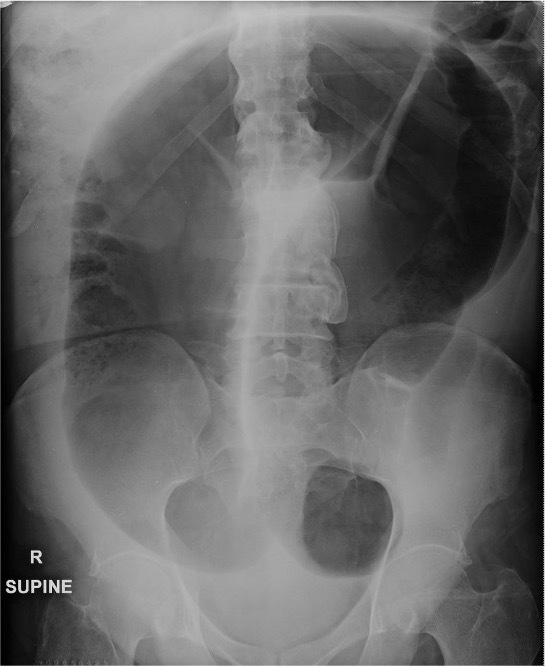

Small bowel obstruction

Large bowel obstruction